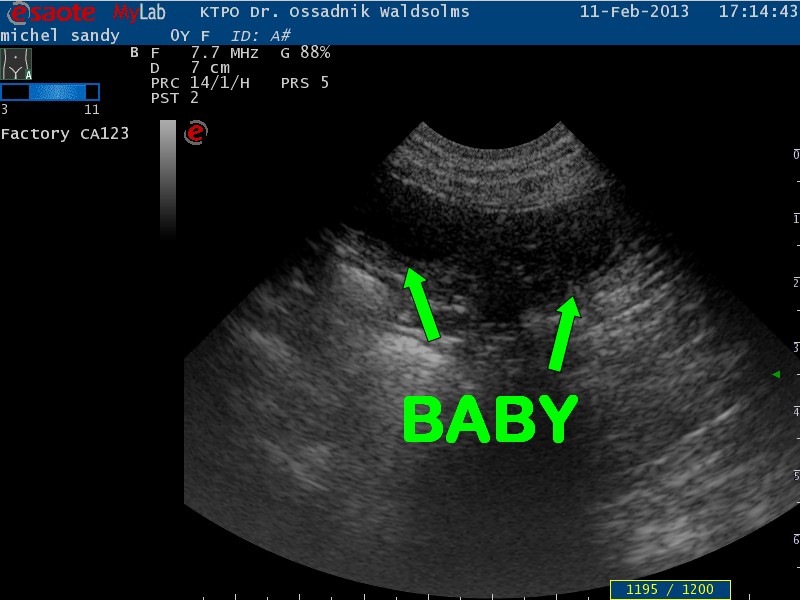

11.02.2013

Siehste, hab ich doch gleich gesagt, BABIES ON BOARD !!!!!!! Sandys Ultraschall hat ganz deutlich 3 Fruchtanlagen dargestellt, auch wenn ich sie selbst sooo deutlich gar nicht sehen kann, Du? Wie viele Babies es tatsächlich sind, kann man aber nicht sagen. Sandy hat das Babykino total gechillt über sich ergehen lassen. Sie hat beim Schallen sogar völlig relaxt ihren Kopf zurückgelegt und das, obwohl sie in Rückenlage ganz still liegen musste. Was ihr allerdings so ganz und gar nicht gefallen hat, war der Schlabber (Schallgel) auf ihrem Bauch und die noch immer kahl rasierte Bauchpartie. Aber was jetzt an Haarkleid weg ist, das muss nicht mehr ausfallen damit die Kleinen später besser an die gute Milch gelangen. Wir sind total stolz auf unsere werdende Mama, sie hat die Untersuchung toll gemeistert !!! Und Papa Ben....der hat derweil zu Hause ganz tapfer auf seine Frau gewartet :D